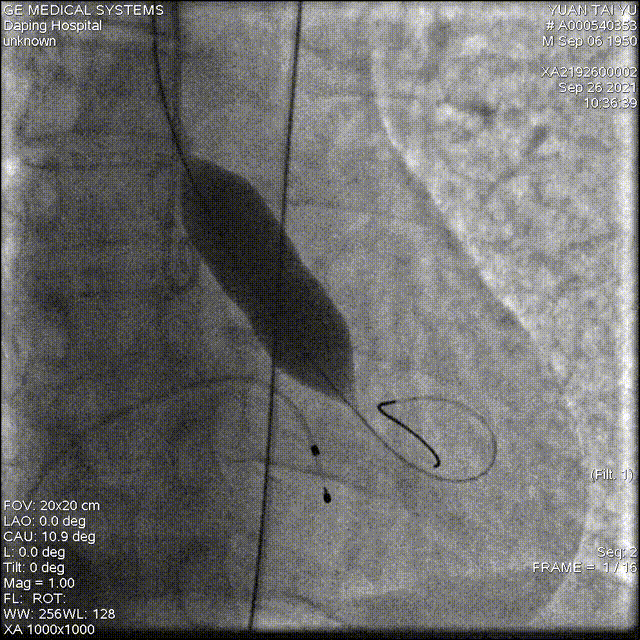

术中影像

以 Seldinger法穿刺右桡动脉,行PCI后,使用PIG造影管行主动脉根部造影

22mm球囊预扩

造影确定输送器位置

高位释放瓣膜